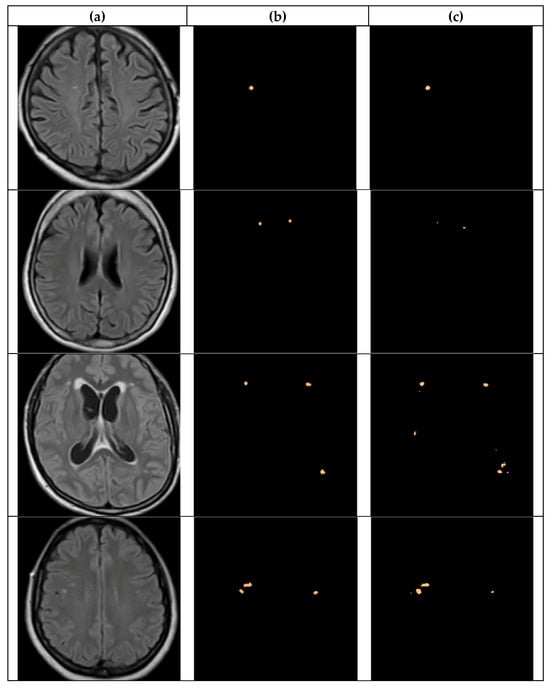

4.2. Segmentation Results

4.2.1. UNet Segmentation

4.2.2. SAM Model